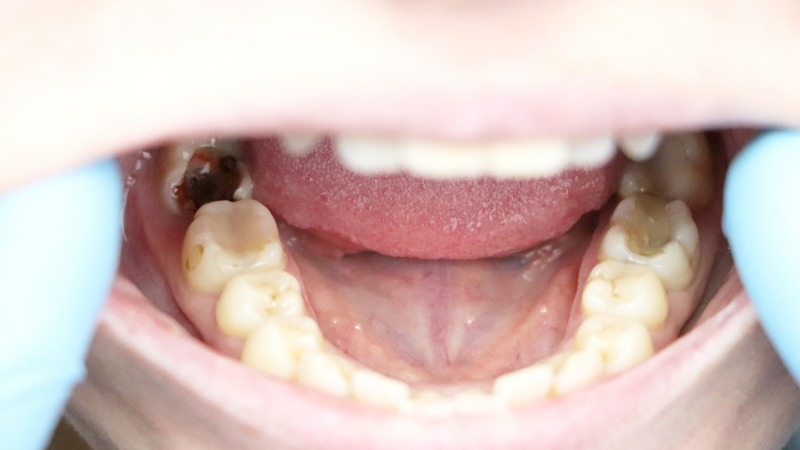

② 歯根の感染・膿が原因の腫れ(根尖性歯周炎)

歯の根の先に細菌が感染し、膿の袋(根尖膿瘍・歯根嚢胞)ができると、歯茎が局所的にぷっくりと腫れることがあります。

これは「根尖性歯周炎」と呼ばれる症状で、過去に神経を取った歯や、虫歯が深く進行した歯に起こりやすいとされています。

歯茎の表面に「ニキビのような膨らみ(フィステル・サイナストラクト)」が現れる場合、そこから膿が排出されている可能性があります。

この症状は自然に治ることはほぼなく、放置すると周囲の骨や隣接する歯茎へ炎症が広がる危険があります。

レントゲン撮影による診断が不可欠で、歯科医院での根管治療(歯の根の治療)が必要になります。